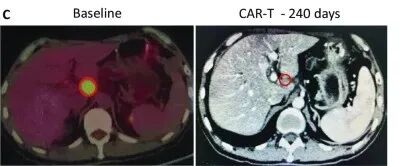

受试者GD-G/M-005 是一例具有 MSLN 表达的晚期胰腺癌患者。该受试者进展为局部淋巴结转移(24×33 mm)(图c)。抗 MSLN-7 × 19 CAR-T 细胞首先通过肝动脉输注,当晚伴有高烧,没有细胞因子释放综合征 (CRS) 或神经毒性。随后,他每1~2个月接受一次抗 MSLN-7×19 CAR-T 细胞的静脉输注。

直到增至CAR-T细胞输注的5倍,CT分期显示他在治疗240天后达到完全缓解,测定的淋巴结为8.3×9.6mm,并未见其他肿大的淋巴结(图C),患者此时病灶完全消失,保持正常状态。